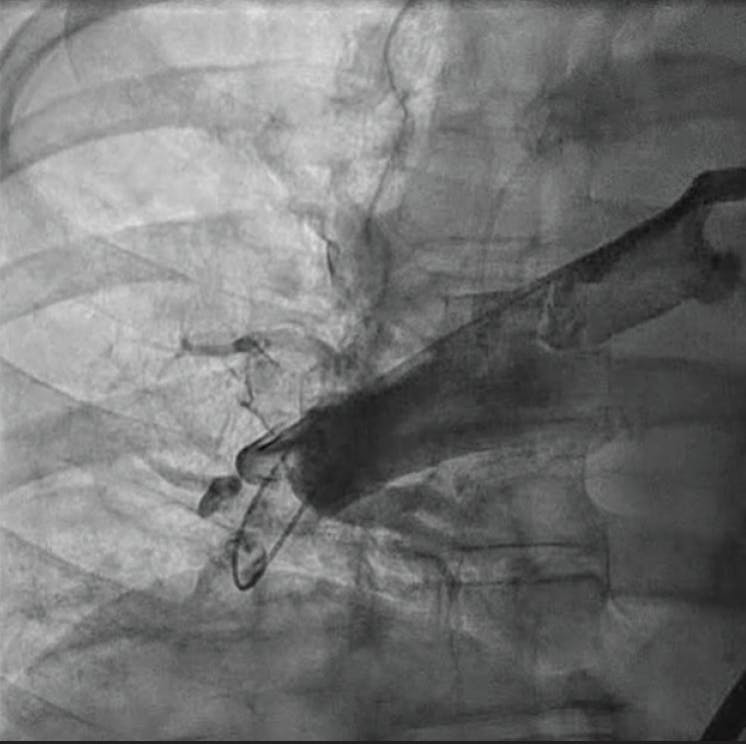

Figure 3. Clot removed.